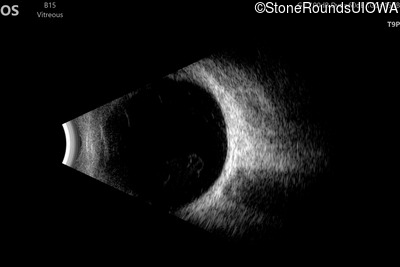

AD Familial Exudative Vitreoretinopathy (IIIE2b)

Age at visit: 23 months

OD OS

This 23 month old male has had nystagmus since shortly after birth. He was born at term (7lbs 12oz).